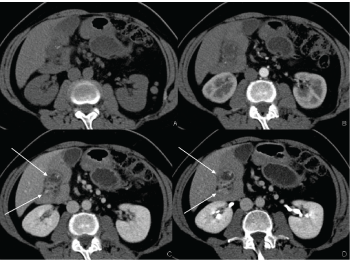

Due to high values of CA 19.9, a thoracic and abdominopelvic enhanced Computed Tomography (CT) was executed (Figure 1, Figure 2, Figure 3 and Figure 4). The examination showed various pathologic findings: First, an oval paraduodenal lesion with a cluster of cystic-like structures (Figure 1), then a second lesion with analogous characteristics not dissociable from the gastric fundus (Figure 2), and the presence of a gastric duplication (Figure 3), finally an anomalous disposition of the entire small bowel and colon and an inversion of the superior mesenteric artery and vein (Figure 4). No pancreatic anomalies were present, the caliber of the Wirsung and secondary pancreatic ducts were normal. Chest CT showed was negative for pulmonary metastases.

Figure 1: Contrast enhanced CT: Lesion of the gastric fundus Non-enhanced CT (A), arterious phase (B), venous phase (C) and coronal reconstruction (D) showing multiple small, clustered cystic foci combined in a lesion not dissociable from the gastric fundus (arrowhead in C). Two calcifications are well visible (arrow in A). View Figure 1

Figure 2: Contrast enhanced CT: Periduodenal lesion Non-enhanced CT (A), arterious phase (B), venous phase (C) and coronal reconstruction (D) Venous phase demonstrating clustered small cysts conjoined in periduodenal region (arrows in C and D). View Figure 2